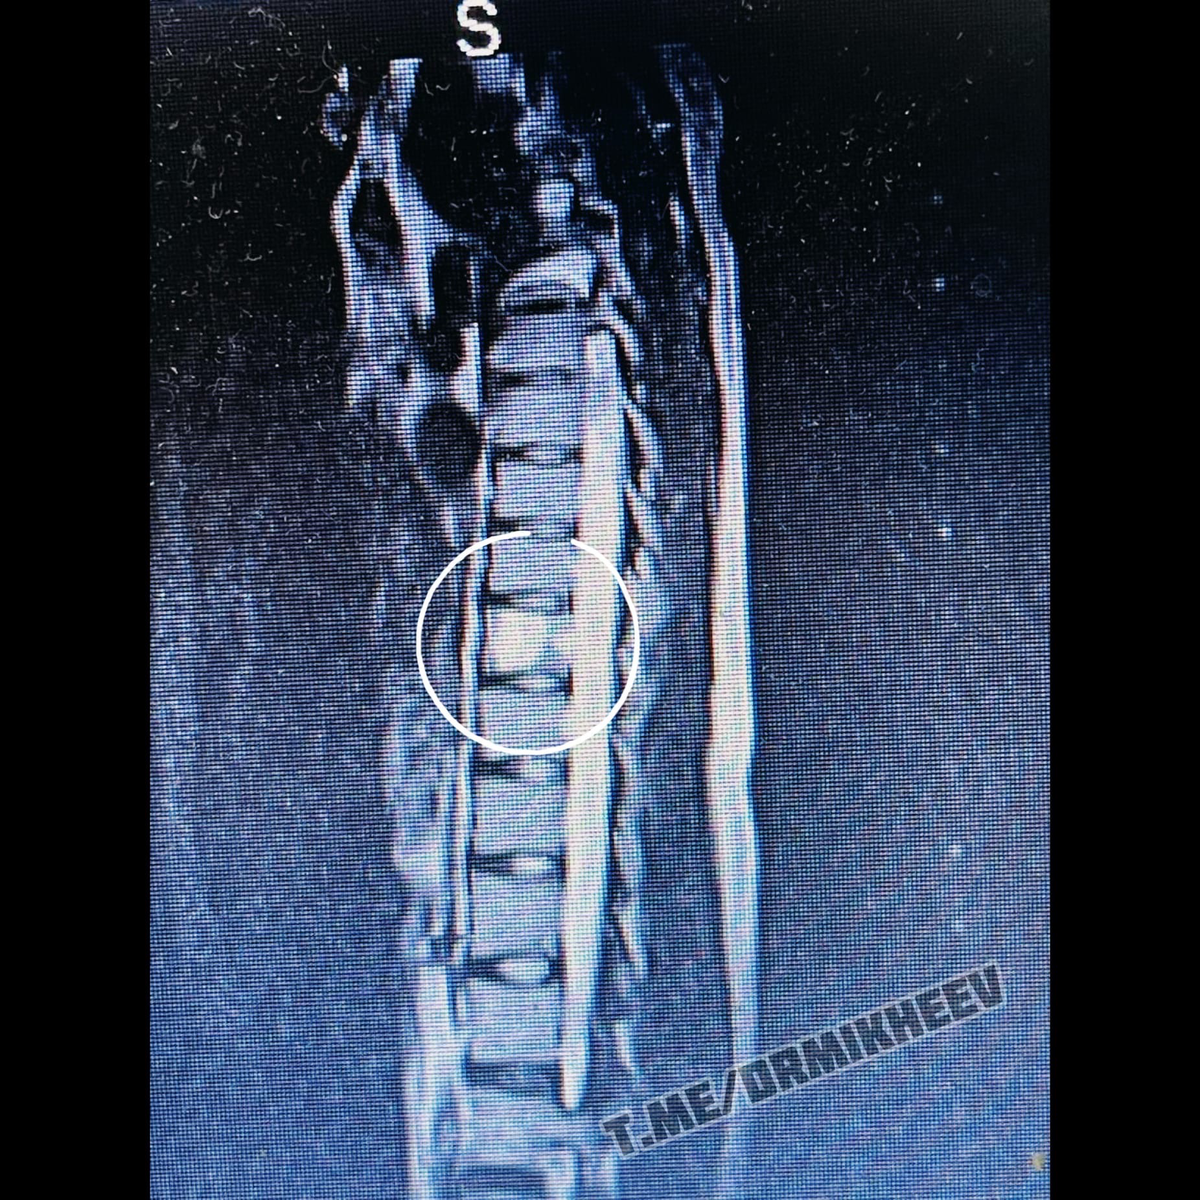

На фото МРТ тех самых пациентов.(двоих из трёх)

⚡️ГЕМАНГИОМА ПОЗВОНКА

Рабочие ситуации. В разные дни пришли три разных пациента. Молодая девушка, молодой человек и женщина 50 лет. Имея при себе актуальное МРТ.  Жалобы практически схожи. Боль между лопаток, в груди, тяжесть в руках, по утрам опоясывающая боль, плохой сон и тд.  С ходу можно сказать, что все симптомы характерны для дорсопатии. Или как любят говорить в поликлинике «ВСЕ ПОНЯТНО! У ВАС ОСТЕОХОНДРОЗ! ДЕРЖИТЕ ДИКЛОФЕНАК...» Но есть одно НО! Во первых наличие боли, локальное, в области позвонка, как при пальпации так и в покое. Во вторых, консервативное лечение не эффективно. В третьих у нас есть МРТ🙂 Да и сама симптоматика слишком размыта...  На втором пациенте, я уже предполагал такой исход, пока грузился диск. Ибо жалобы на 90% идентичны.  «Что такое эта гемангиома и чем она опасна?» И раз уж я решил умничать на канале, думаю логично будет сделать небольшой разбор. На фото МРТ тех самых пациентов.(двоих из трёх) Если возьмём статистику по исследованиям данной темы, то увидим, что гемангио